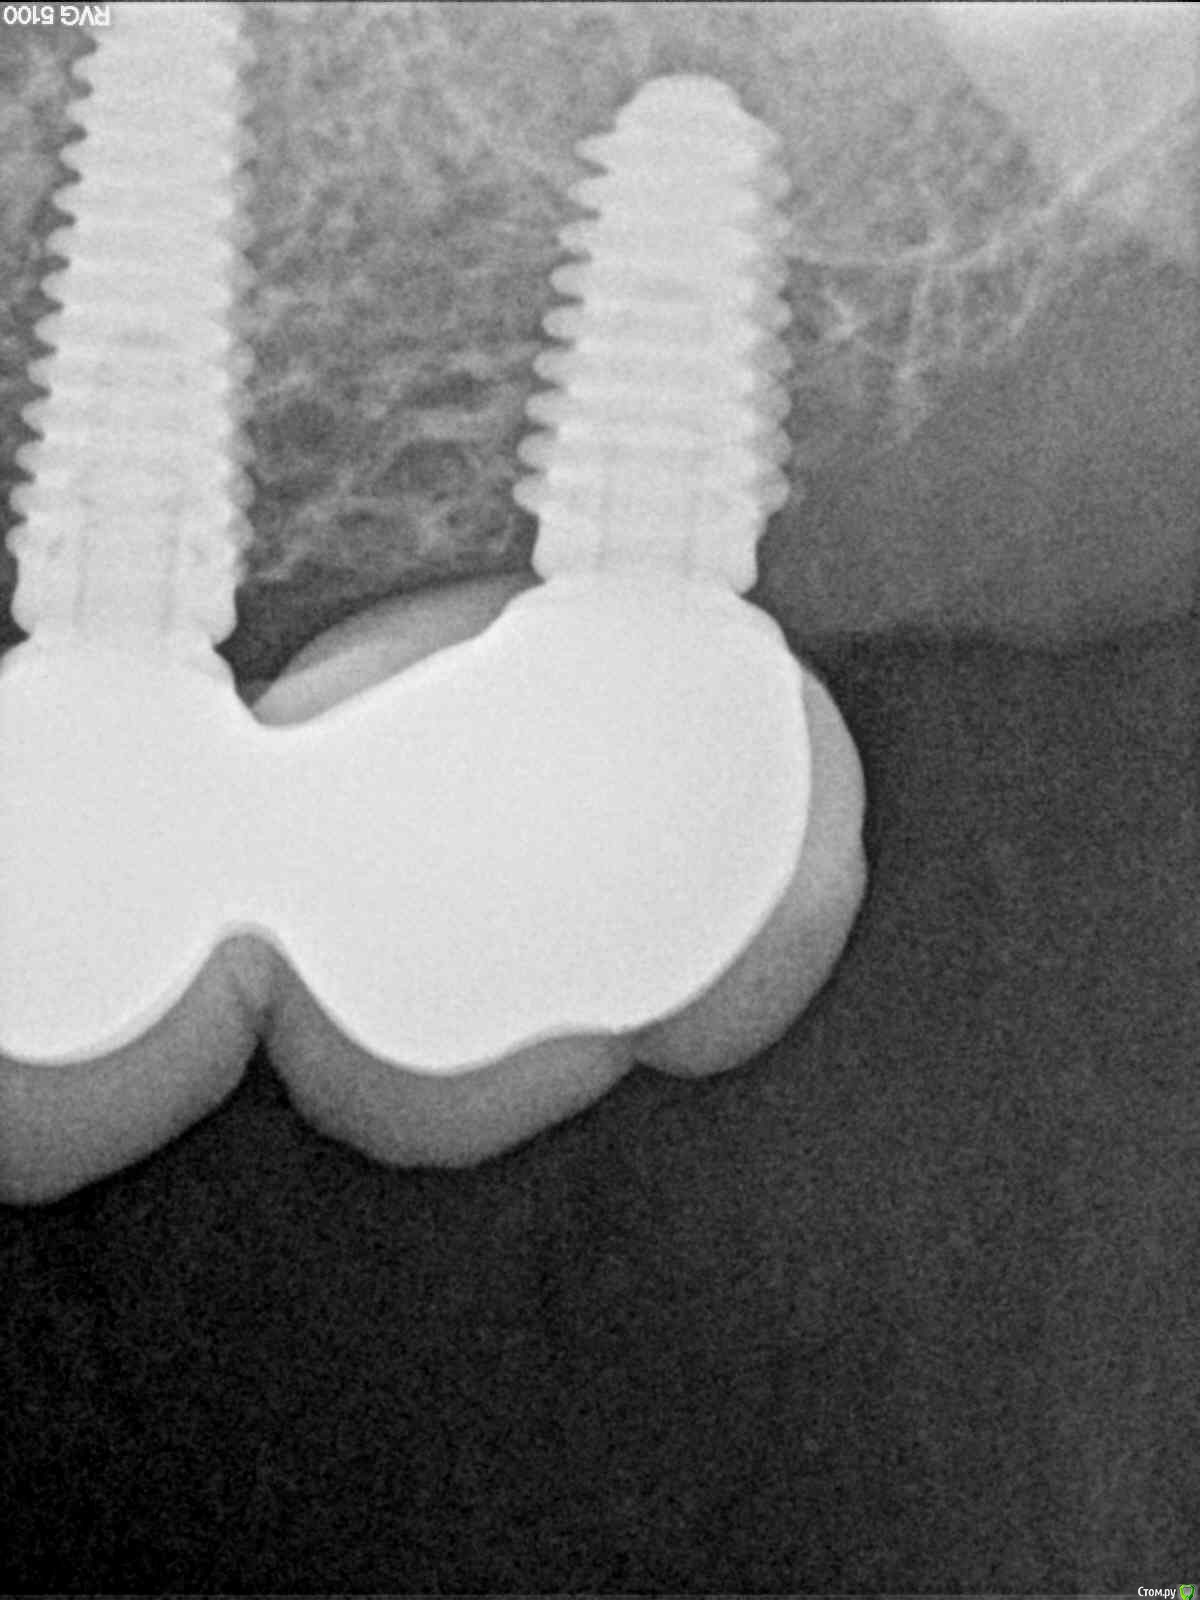

filvik Опубликовано 23 марта, 2017 Автор Поделиться Опубликовано 23 марта, 2017 (изменено) Сфотографируйте коронкиКак-то, так. Изменено 23 марта, 2017 пользователем filvik Ссылка на комментарий

filvik Опубликовано 24 марта, 2017 Автор Поделиться Опубликовано 24 марта, 2017 Как-то, так.К 3-D КТ приложен рентгеновский снимок то, что было в конце в 2013 года, по ниткам резьбыхорошо видна толщина кости в которой сидит дальний имплант (при длине импланта 9 мм.), на КТ 2017 годавидно что с дальней стороны последнего зуба осталось 1,8 милиметра кости.Коронки ставить 1+2 или на каждый отдельно, да и задний имплант похоже держится на честном слове.Вопрос остался прежний что предпринять в данной ситуации? Ссылка на комментарий

filvik Опубликовано 26 марта, 2017 Автор Поделиться Опубликовано 26 марта, 2017 решить вопрос с мягкими тканями. И с костью все будет ок.Обьясни , пожалуйста.Эта коронка с фото (ракурс подкачал, вид как-бы с низу),установлена после наращивания кости и мягких тканей.До операции было 3 коронки (пролежни и тд и тп),это первая коронка в этом году после операции. Ссылка на комментарий

Bier Опубликовано 26 марта, 2017 Поделиться Опубликовано 26 марта, 2017 я вижу на фото дефицит кератинизированной десны и тонкий биотип. Вот это надо поменять и все станет стабильнее.У нас принято общаться на Вы с незнакомыми. 1 Ссылка на комментарий